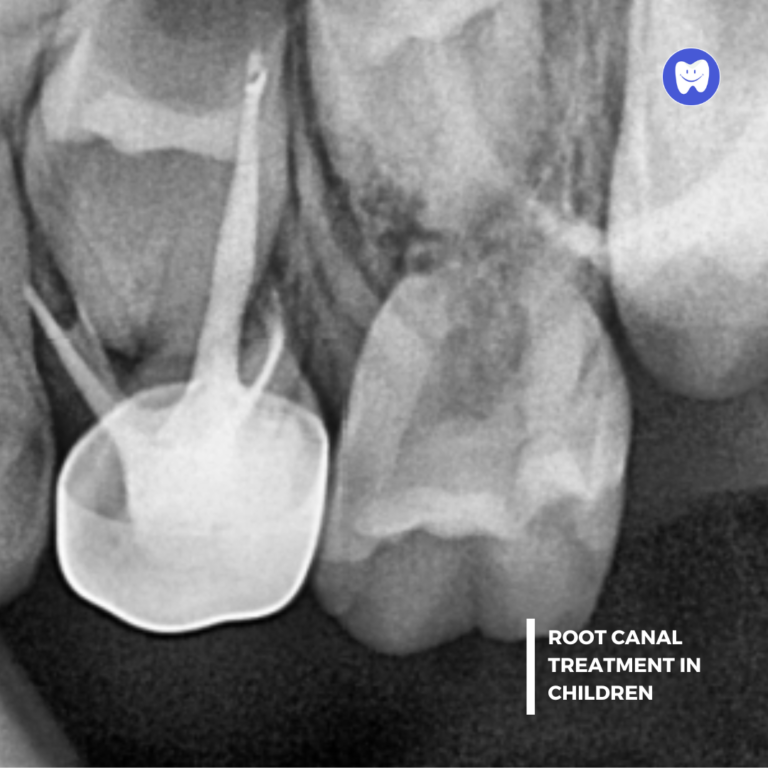

Root Canal Treatment (RCT) is a procedure designed to save a severely damaged or infected tooth by removing the infected tissue inside, cleaning the tooth, and sealing it to prevent further issues. At Kidsville Dental, our gentle approach ensures your child’s comfort throughout the process.

• Thorough examination and digital X-rays to assess the extent of damage.

• Gently removing the infected or damaged pulp tissue.

• Cleaning and disinfecting the inside of the tooth.

• Filling the tooth with a biocompatible material to prevent reinfection.

• Placing a temporary or permanent crown for added protection.